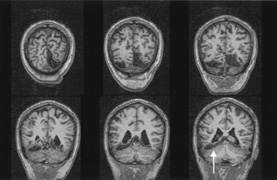

HEMIACHROMATOPSIA.

Achromatopsia in the contralateral hemifield alone can follow unilateral right or left occipital lesions (Fig. 18). Patients are typically asymptomatic until the defect is demonstrated on examination.234,235 Hemiachromatopsia is usually associated with a superior quadrantanopia;234,235,241 therefore, the color defect is only demonstrable in the remaining inferior quadrant. The preserved color vision in the ipsilateral hemifield allows normal or near-normal performance on centrally viewed tests of color vision such as pseudoisochromatic plates. The incidence of hemiachromatopsia is probably underestimated, given its asymptomatic nature and the failure of routine clinical color tests to detect its presence.

Fig. 18. Magnetic resonance imaging scan of patient with stroke causing a right hemiachromatopsia as well as partial superior quadrantanopia.